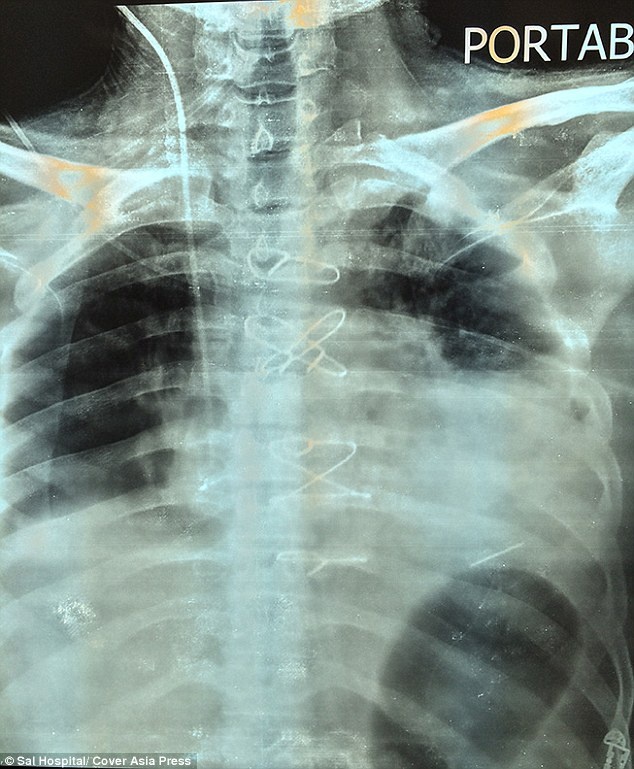

Ο 32χρονος Bharat Sharma, από την Ινδία, δέχτηκε δυο σφαίρες στις 22 Ιουλίου κατά τη διάρκεια ληστείας σε τράπεζα, την ώρα που προσπαθούσε να καταθέσει κάτι επιταγές

Ο άτυχος άνδρας μεταφέρθηκε στο νοσοκομείο όπου οι γιατροί κατάφεραν και αφαίρεσαν τη μια σφαίρα που τον είχε χτυπήσει στη μέση.

Ωστόσο φοβήθηκαν να προχωρήσουν στη δεύτερη επέμβαση, για να βγάλουν τη σφαίρα που τον είχε βρει ελάχιστα χιλιοστά από την καρδιά του!

Τελικά, μια ομάδα γιατρών σε νοσοκομείο της Gujarat στην Ινδία ανέλαβε την επικίνδυνη επέμβαση που έγινε με επιτυχία στις 23 Σεπτεμβρίου, δυο μήνες δηλαδή μετά το περιστατικό.

Όπως αναφέρει η Daily Mail ο τυχερός, μέσα στην ατυχία του, άνδρας θα μπορούσε να είχε πεθάνει καθώς η σφαίρα απείχε ελάχιστα από την καρδιά του.

Έτσι ζούσε για δυο μήνες με τη σφαίρα μέσα του.